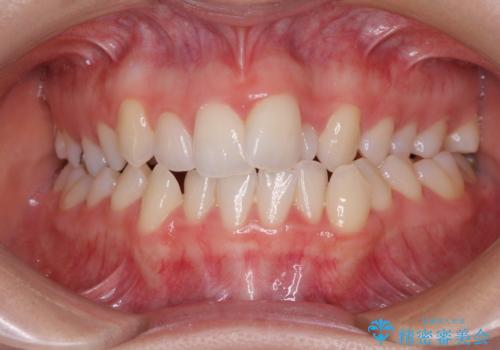

非抜歯、ワイヤーでの矯正治療。歯のがたつき、顎のズレ、出っ歯を治す。インビザラインが使えない方